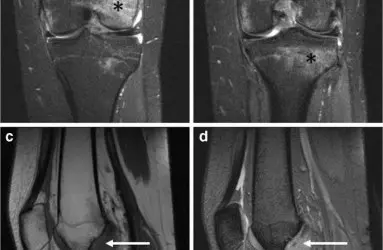

- Artroskopi

- Diz Ekleminde Kireçlenme (Diz Osteoartriti)